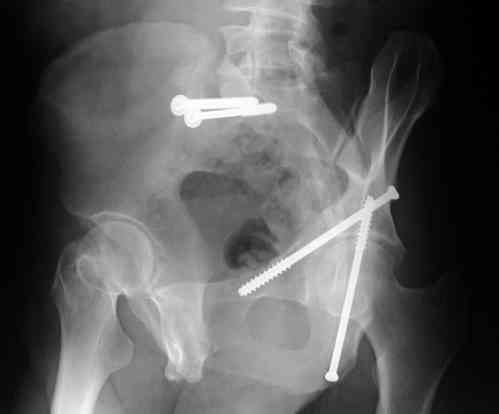

I'll include a few images of a similar injury in a similarly large male patient. This patient "showed up" in our ER c/o hip pain 2 months after being treated in the lateral position, without a quality reduction, without an anterior column transverse supporting implant, with an unbalanced plate applied too medially, with insufficient caudal segment fixation...it took over 8 hours and a 3+ l blood loss to debride the callus from front then

back, excise the HO, release his sciatic nerve, reduce the head-transverse-wall, and fix it...and now it's a staging procedure.